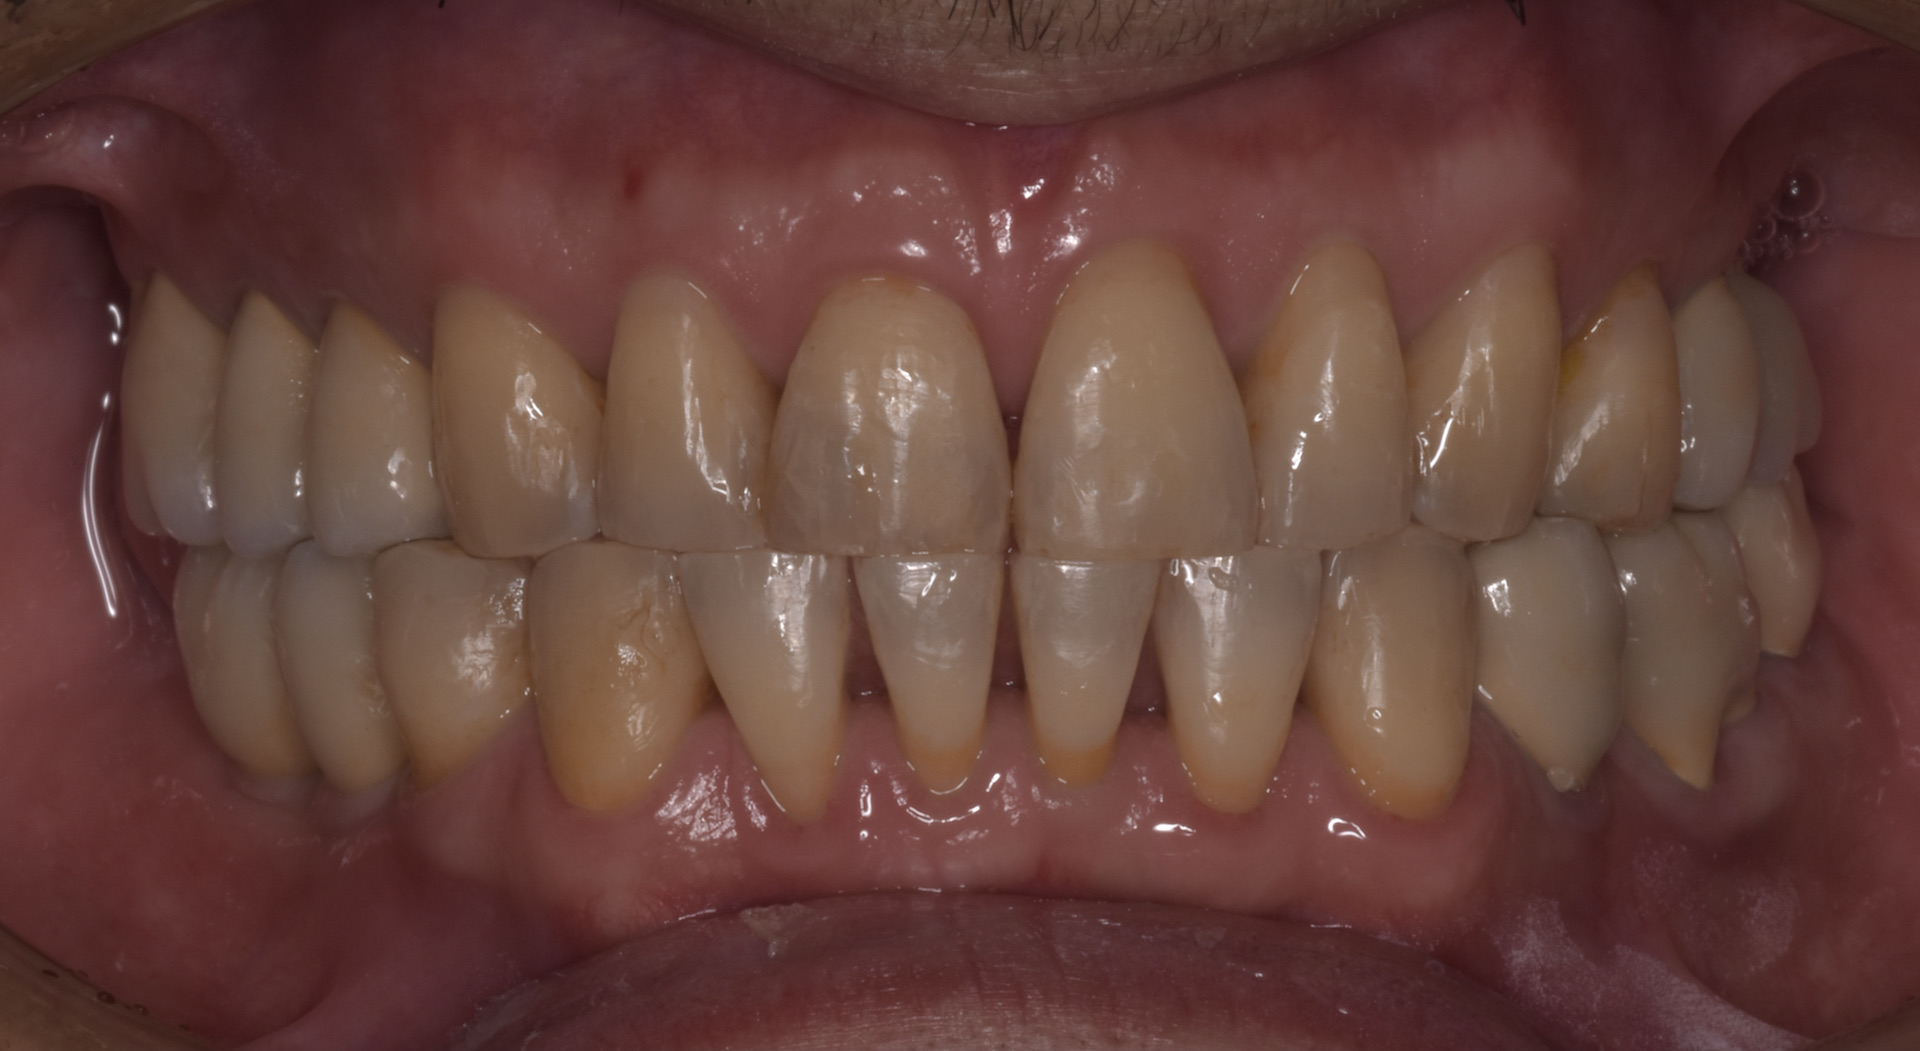

治療後

抜歯後は私の予測通り、長年治らなかった顎関節の症状が全く消失しました。つまり今までの顎の痛みの原因は、咬み合わせが原因という事になります。

原因がわかり理解出来れば歯が無い箇所はインプラント治療を行い、精密な虫歯治療の後にセラミック治療を行って正しい咬み合わせを構築しました。

T-Scanを使って咬み合わせの調整をしてすべての歯が均等に当たるように治療を致しました。この治療のように咬む力で問題が起こっている場合には、デジタル機器をきちんと用い、データを採りながら患者さんの咬んだ印象も参考にして治療を進めていくのは大切な事です。